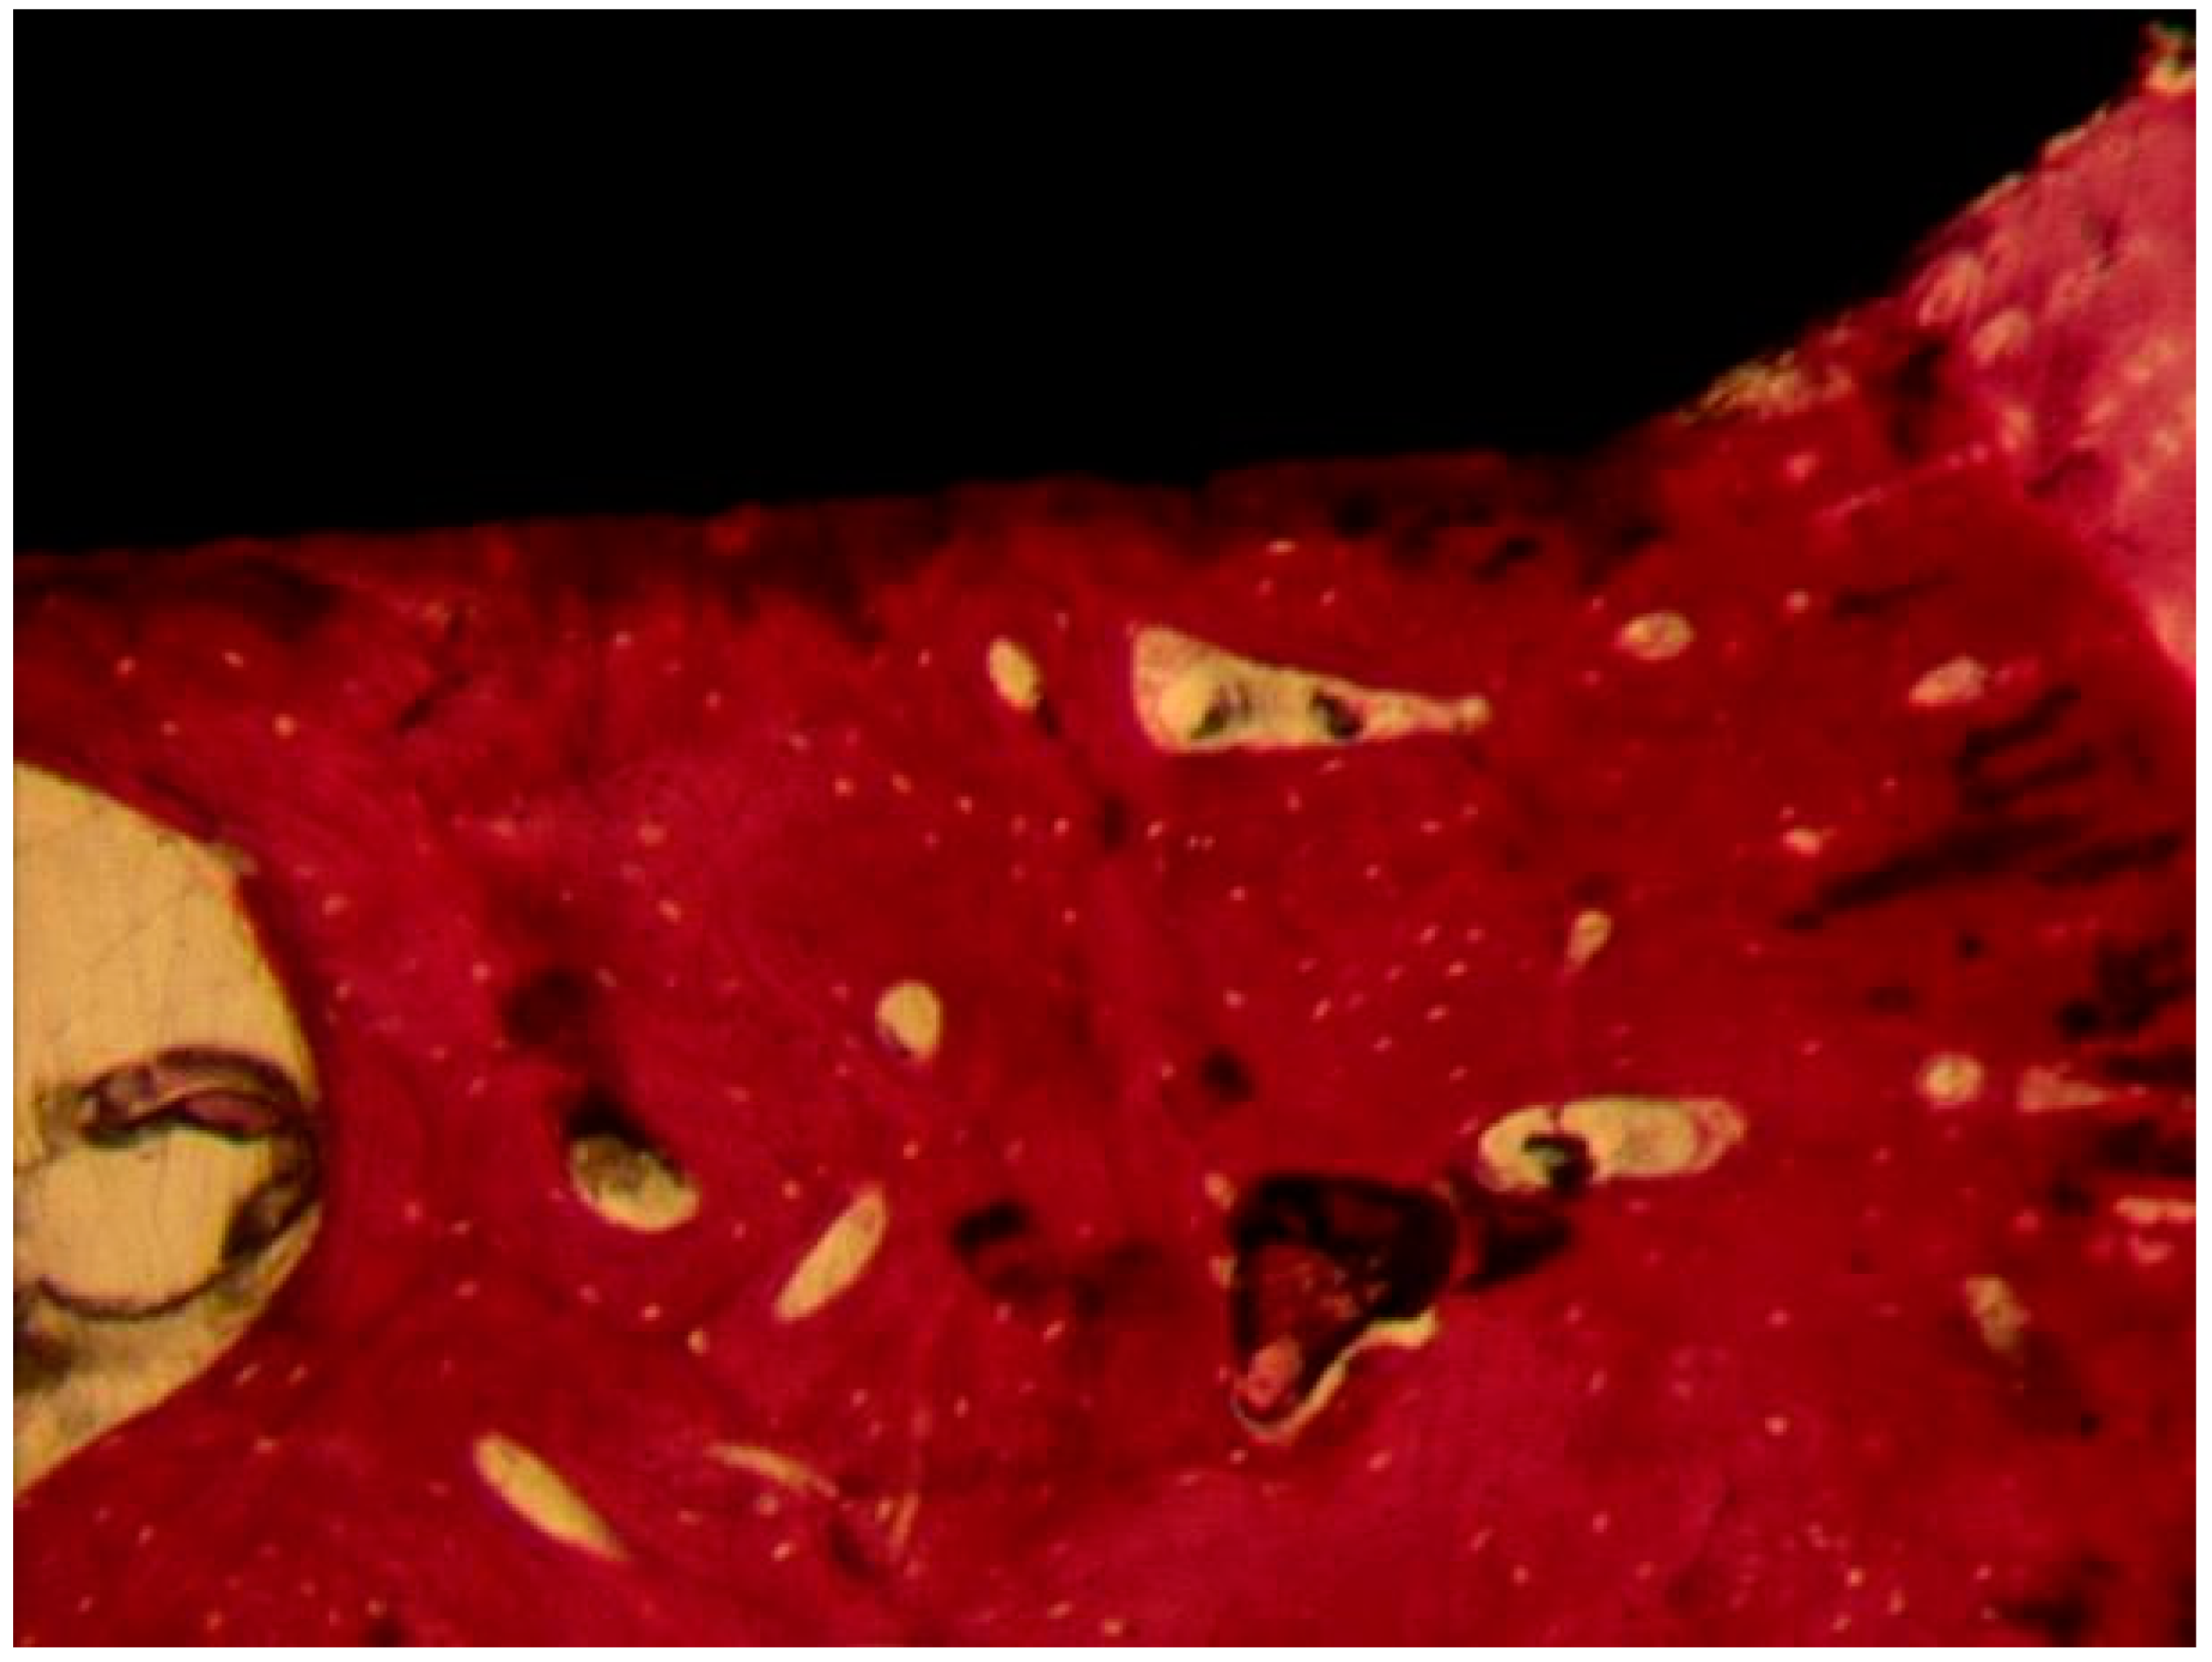

Coated Implant Surface

The mature bone was present (Figure 11). Only in a few areas of the interface, the osteoid matrix not yet mineralized was still present. No inflammatory cells were present. No gaps were present at the bone-implant interface. BD was 56.8 ± 1.4%, BIC was 57.3 ± 2.4%, bone area inner threads (BAIT) was 38 ± 4.2%, and bone area outer threads (BAOT) was 36 ± 3.5%.

Figure 11.

The mature bone was observed at the interface with the implant. Acid fuchsin-toluidine blue 100×.